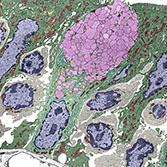

Histology is the study of the microanatomy of cells, tissues, and organs as seen through a microscope. It examines the correlation between structure and function.

Histology Guide teaches the visual art of recognizing the structure of cells and tissues and understanding how this is determined by their function. Rather than reproducing information found in a histology textbook, a user is shown how to apply this knowledge to interpret cells and tissues as viewed through a microscope.

An Aperio slide scanner was used to obtain a high-resolution image of each slide in its entirety. Large tissues are up to 34 GB for a single, uncompressed image of 150,000 x 75,000 pixels.

The contrast, color, and sharpness of each image were adjusted to at least maintain the appearance of the tissue as seen through a microscope. In many cases, these adjustments improved upon their visual appearance.

Unlike low-resolution images, users can interactively explore these large images by zooming-and-panning in real-time. A software-based virtual microscope (Zoomify HTML5 Enterprise) allows the examination of large and small structures in the same specimen.